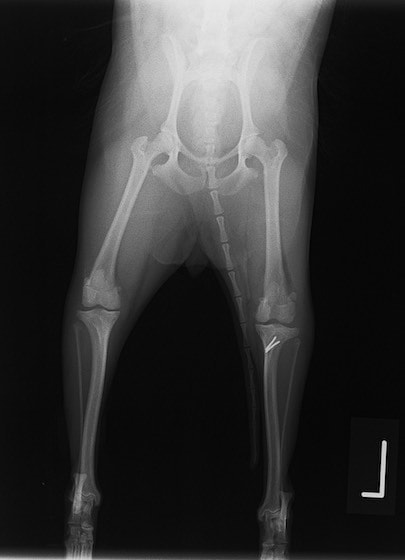

■ 症例24 キャバリア 7か月

左右膝蓋骨内方脱臼(左:グレードⅣ 右:グレードⅢ)

以前から左右後肢の跛行が認められ、整形外科学的検査・レントゲン検査により左右の膝蓋骨脱臼が認められた。症状が重度である左膝の膝蓋骨脱臼整復術を行った。外科手技は縫工筋及び内側広筋の解放、脛骨粗面の外側転位、滑車ブロック形造溝術、内外側関節方の縫縮を実施した。術後一か月時点で、左の膝蓋骨は安定しており経過は良好である。

本症例は成長期における重度の膝蓋骨脱臼であり、術後の再発の可能性もあるため、経過をしっかりと観察していく必要がある。また、今回手術を実施していない右膝に関しても経過を観察し、手術を検討していくこととする。